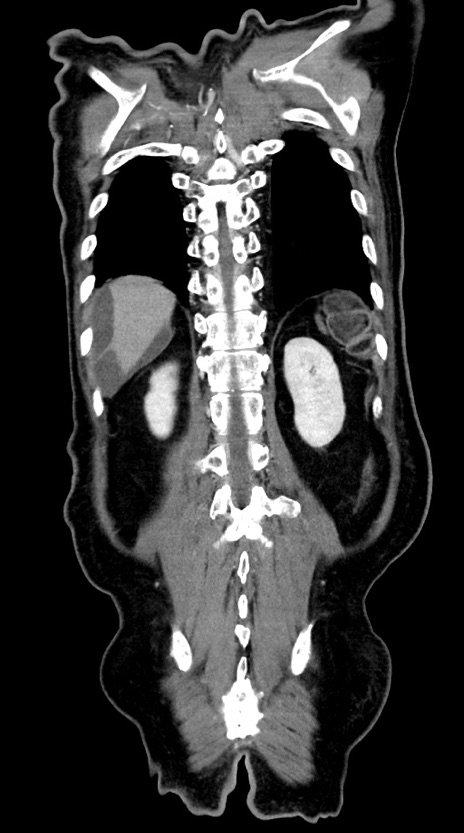

横断像

【症例】60歳代男性

【主訴】嘔吐

【現病歴】胃癌にて胃全摘後。食思不振が悪化し、夜中に嘔吐することがある。

【既往歴】胃癌、胃全摘、脾摘、胆摘後

【データ】WBC 5900、CRP 10.56